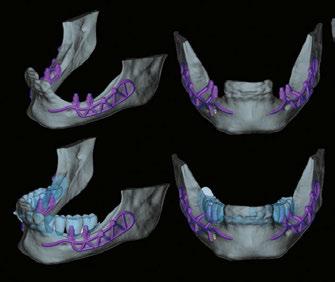

Newer patient-specific implants use modern CBCT and patient scanning technology to create custom-milled patient specific subperiosteal implants. The authors selected Panthera Dental as their partner to design and manufacture this patientspecific subperiosteal implant. Nevertheless, other companies like Bone Easy® and KLS Martin also provide similar implants.

• A cone beam scan exported in DICOM format. The success of the treatment depends largely on the accuracy and quality of the CT data. It is therefore advisable to opt for a large acquisition field, covering the entire mandible up to the posterior ascending ramus. In addition, the highest possible image resolution and the use of metal artifact reduction tools (such as the CS “MAR” — Metal Artifact Reduction) are essential to ensure optimal implant adaptation (Figure 1).7

• An optical impression of the dento-mucosal surfaces.

• This is all combined with a digital wax-up, a preview of the future prosthetic project which will be exported in STL or PLY format. In the case of a limited number of residual teeth, radiopaque markers can be used to help combine the three types of data (Figure 2).8,9

DICOM and STL files are transferred to the Panthera online platform. Once the order has been placed, a viewer allows you to follow and validate the implant creation stages (Figure 3).

Implant modeling is performed by the company’s designers using their proprietary software, adapting to the clinical case and respecting a common structure. At the vestibular level, the exoskeleton bypasses the chin (mental foramen) foramen, while osteosynthesis screws positioned more posteriorly stabilize the implant on the cortex of the external oblique line. A loop extends and completes the structure on the lateral surface of the ascending branch.

Figure 1: Initial CBCT examination (Carestream 9600)

Figure 2: Optical impression (Primescan – Densply Sirona) and prosthetic project based on the antagonist arch (Design4me)

Figure 3: CBCT, optical impression, and digital wax-up uploaded to the Panthera platform dashboard

Figure 4: Subperiosteal implant design on the Panthera Dental platform. (Vestibular, frontal, occlusal, and lingual views)

Lingually, the framework forms a loop in the retro-symphyseal region and stops at the most distally located abutment, remaining coronal to the mylohyoid line (Figure 4).

Thanks to the evolution of materials, the development of digital tools, and the improvement of production techniques, Panthera is able to manufacture subperiosteal implants in grade 23 6AL 4V ELI titanium discs using 5-axis milling machines with a precision of 5 mm. Finally, the surface finish is sandblasted in areas in contact with bone and the periosteum to promote bone regeneration.10.11

Implants are supplied with a 3D resin model of the jaw. This model is used to check that implants fit perfectly before they are inserted. It also helps the operator find the ideal insertion axis, which should be achieved by distal translation followed by mesio-lingual rotation. This movement may differ slightly from one patient to another (Figure 5).